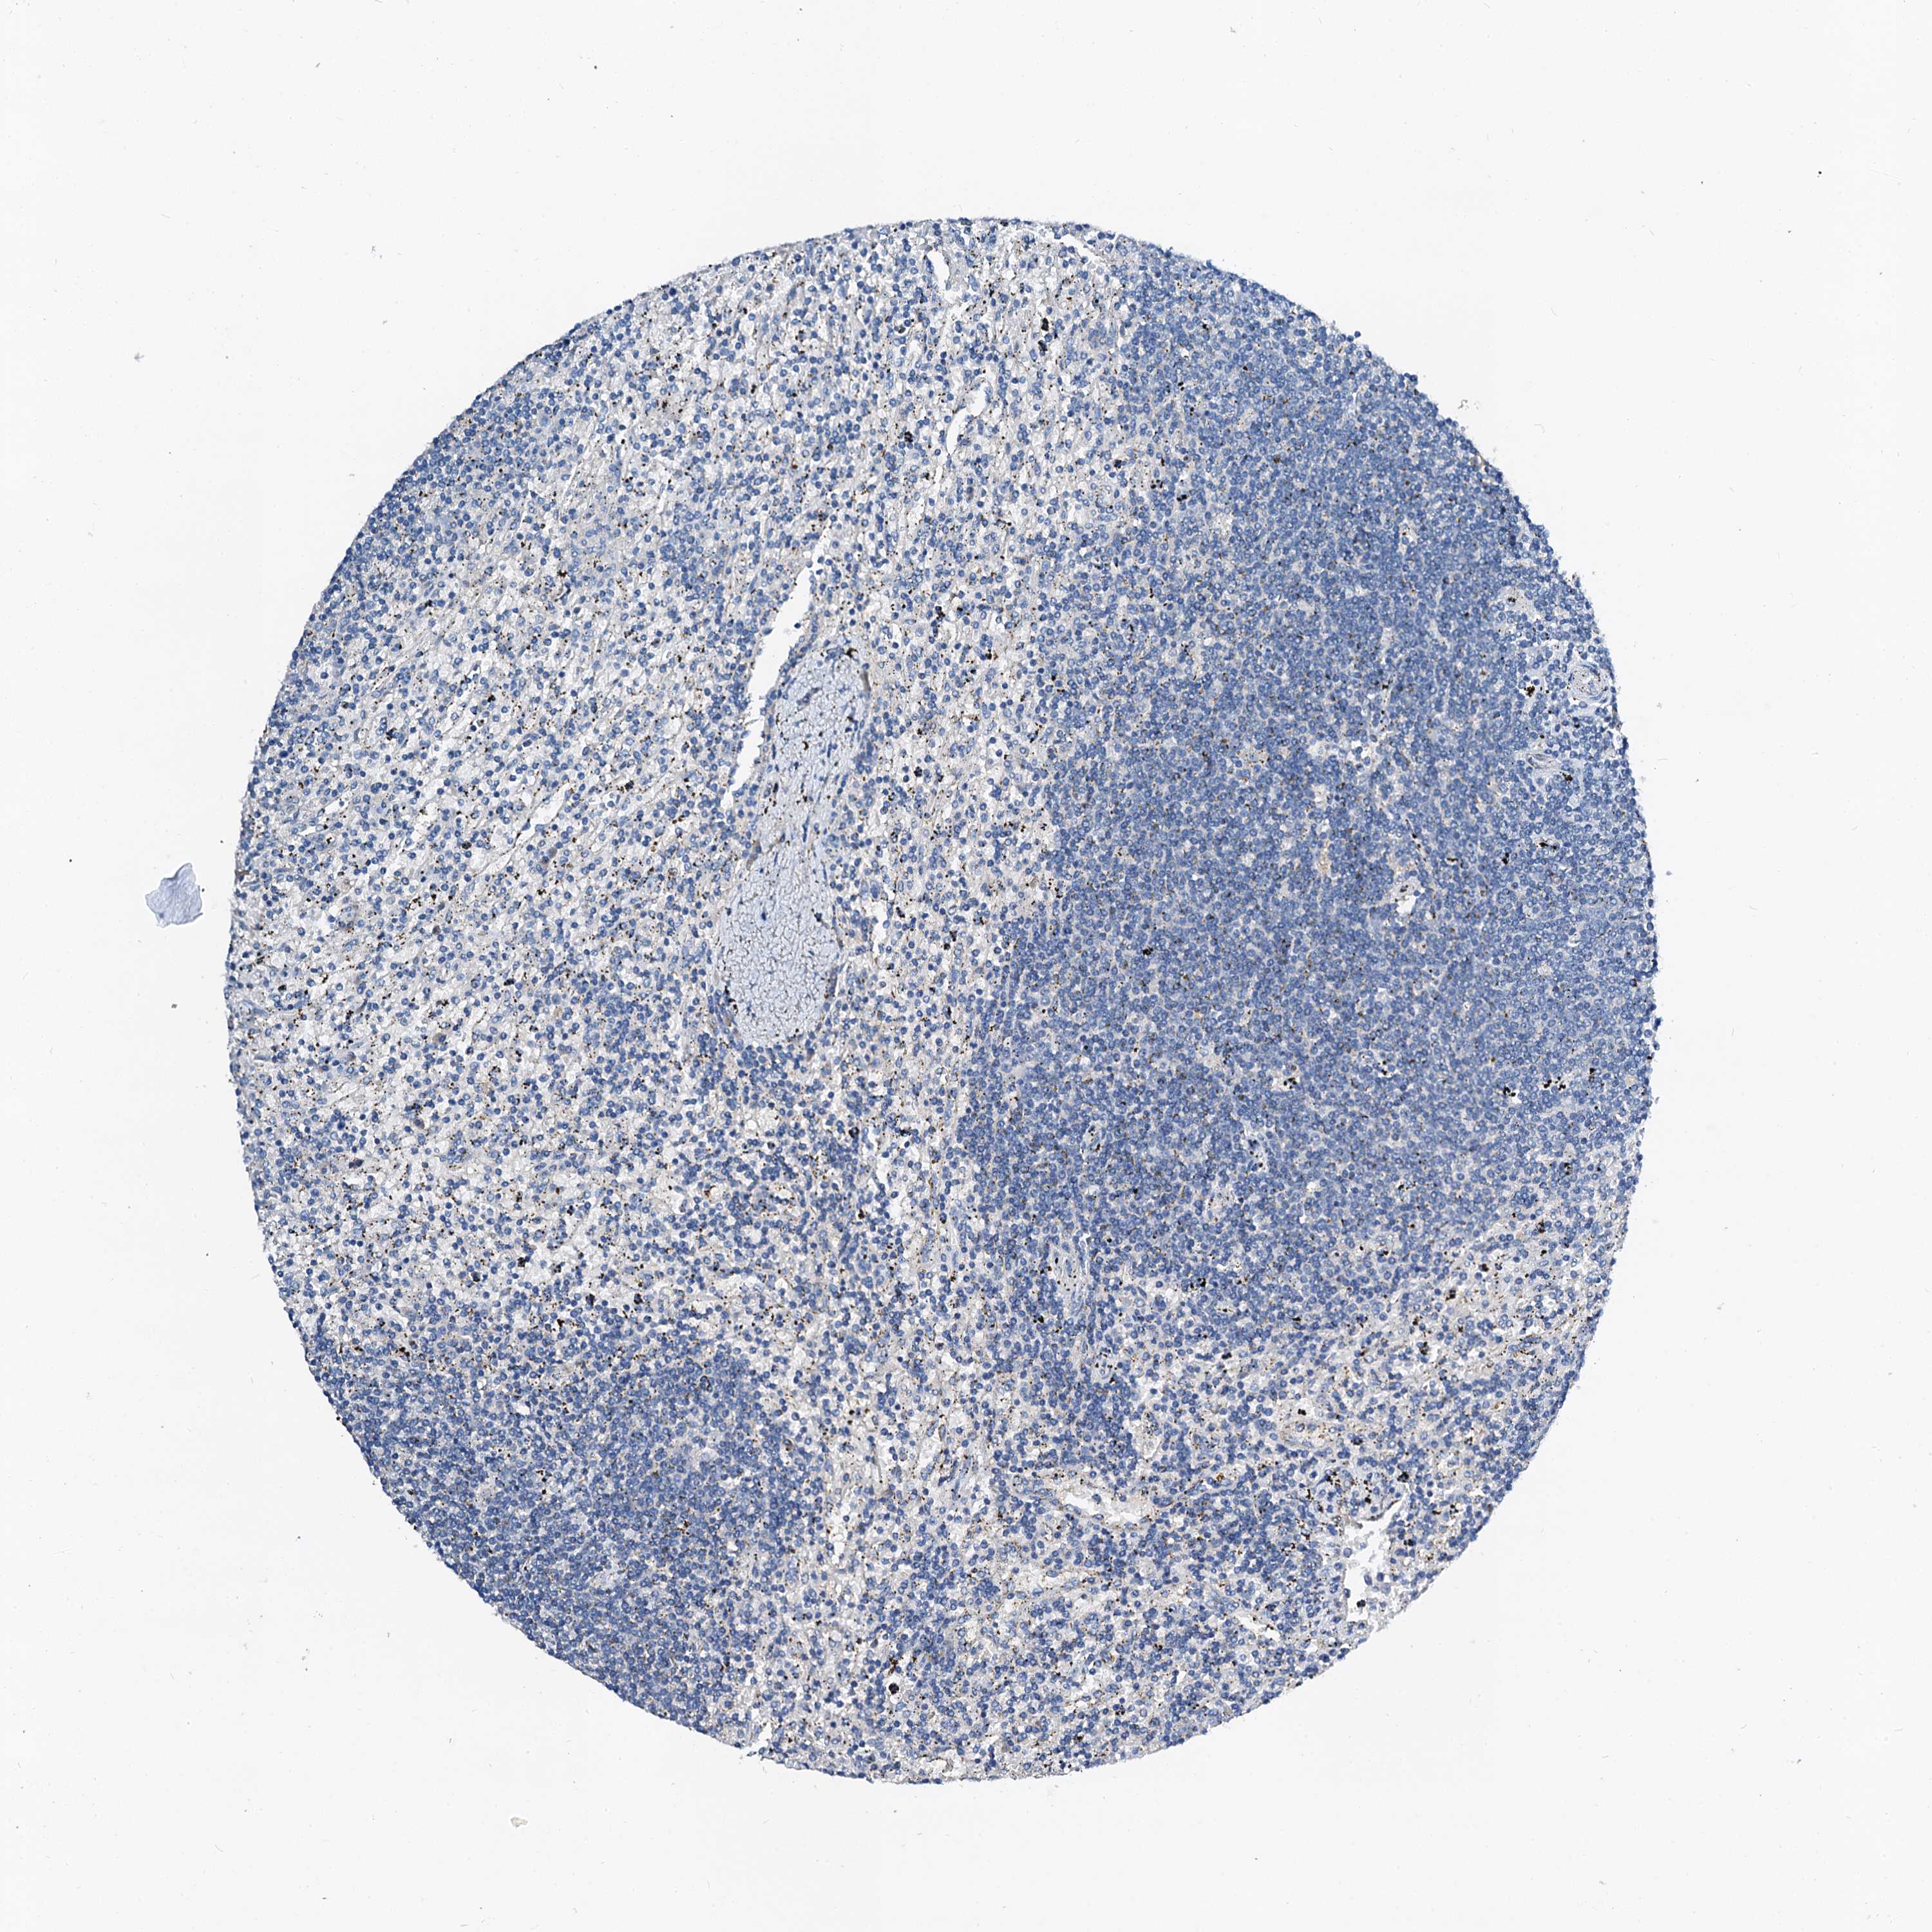

LYMPHOMA - Protein expressioni

A mouse-over function shows sample information and annotation data. Click on an image to view it in a full screen mode. Samples can be filtered based on level of antibody staining by selecting one or several of the following categories: high, medium, low and not detected. The assay and annotation is described here.

Antibody stainingi

Antibody staining in the annotated cell types in the current human tissue is reported as not detected, low, medium, or high, based on conventional immunohistochemistry profiling in selected tissues. This score is based on the combination of the staining intensity and fraction of stained cells.

Each image is clickable and will lead to virtual microscopy that enables deeper exploration of all samples and also displays staining intensity scores, fraction scores and subcellular localization as well as patient and tissue information for each sample.

Antibody HPA040120

Staining

High

Medium

Low

Not detected

Intensity

Strong

Moderate

Weak

Negative

Quantity

>75%

75%-25%

<25%

None

Location

Nuclear

Cytoplasmic/membranous

Cytoplasmic/membranous,nuclear

Hodgkin's disease, NOS

Malignant lymphoma, non-Hodgkin's type, High grade

Malignant lymphoma, non-Hodgkin's type, Low grade